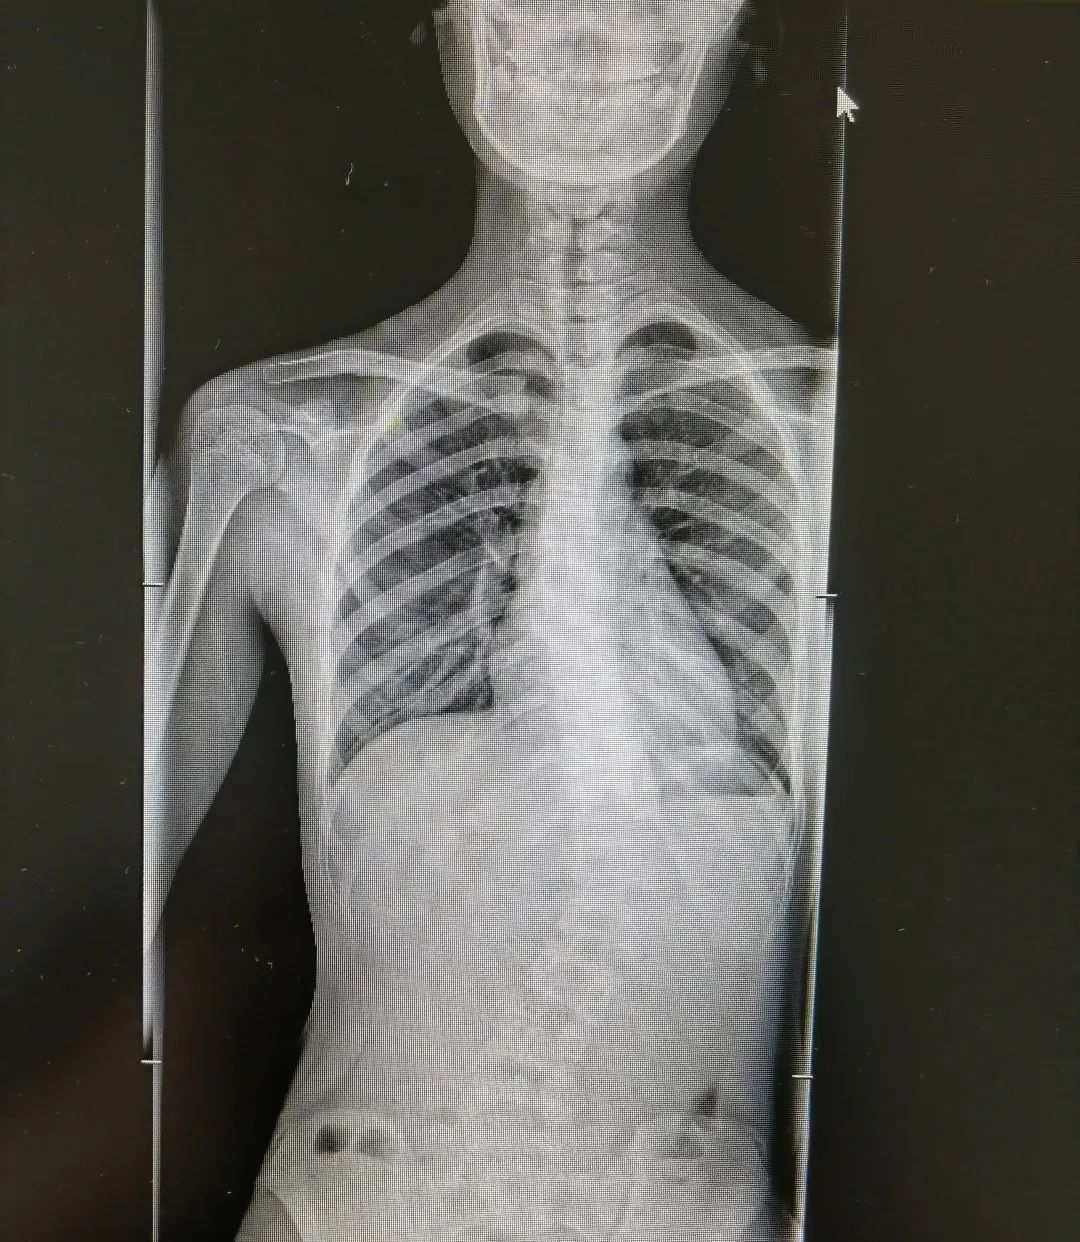

青少年特发性脊柱侧弯术前术后图

“在所有脊柱侧弯类型中,临床中占比最高、最常见的就是青少年特发性脊柱侧弯,约占脊柱侧弯的百分之70%。目前它的发病原因尚不清楚,可能与遗传、免疫、激素、姿势不良等因素有关,往往从10岁左右开始发病。根据严重程度不同,治疗方案也有差异。部分患儿可以采用支具矫形、物理康复锻炼等方式进行保守治疗,但是如果侧弯度数大于40°,就需要考虑手术矫形。”

陈文昊副主任表示,虽然青少年特发性脊柱侧弯目前病因不明,但部分患有青少年特发性脊柱侧弯的孩子都有一个特点——短时间内长得都比较快。青春期骨骼快速生长发育,原本轻微的脊柱侧弯此时也会迅速进展,一年甚至可长歪10度以上。